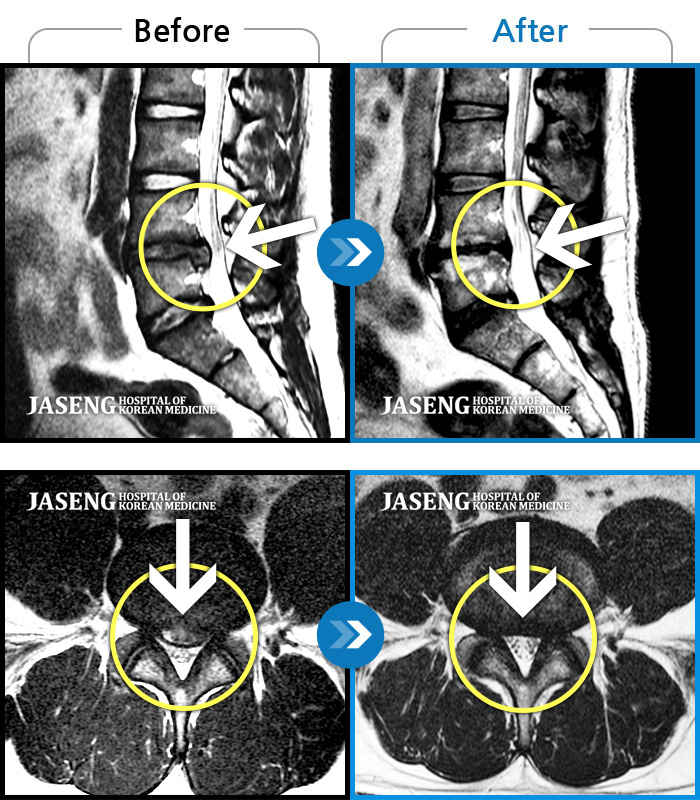

허리디스크

강남 · 강만호 원장

허리 통증 및 왼쪽 다리 근력저하 감각저하로 일상생활이 불가능했습니다.

촬영시기

2024.05.18 ~ 2025.12.03

2025.12.19